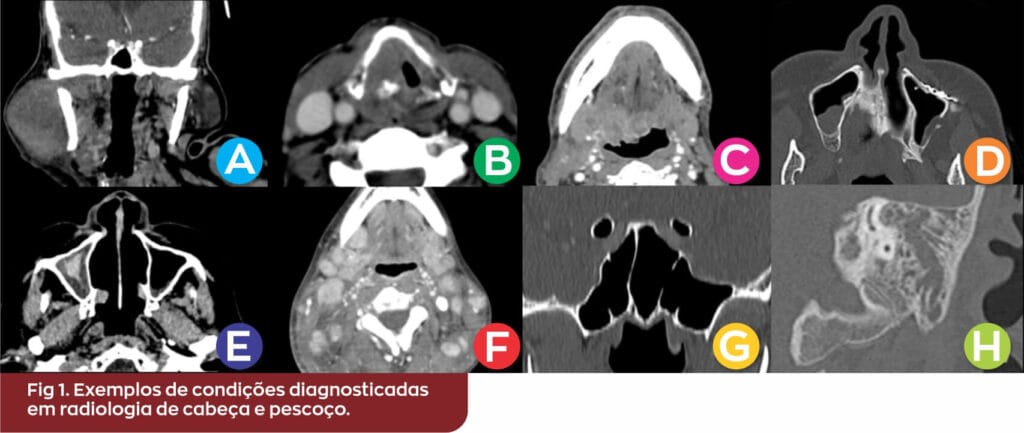

Fig 1. Exemplos de condições diagnosticadas em radiologia de cabeça e pescoço.

(A) Reformatação coronal de TC cervical pós-contraste. Formação neoplásica expansiva parotídea à direita em paciente com história de abaulamento local e tabagismo de longa data.

(B)  TC axial cervical pós-contraste. Lesão infiltrativa na glote direita, determinando redução da coluna aérea laríngea, representando carcinoma escamocelular.

(C) TC axial cervical pós-contraste. Extensa neoplasia expansiva ulcerada na base da língua, protruindo para a coluna aérea da orofaringe, especialmente à direita. Linfonodos cervicais suspeitos para acometimento secundário foram evidenciados em diversos níveis (não demonstrado).

(D) TC axial dos seios paranasais janela óssea. Alterações pós-operatórias de trauma na parede anterior do seio maxilar esquerdo, com material de ostessíntese local.

(E) TC axial dos seios paranasais janela de partes moles. Conteúdo hemático e espessamento do revestimento mucoso no seio maxilar direito em paciente com epistaxe.

(F) TC axial cervical pós-contraste. Linfonodos cervicais aumentados em número e várias linfonodomegalias homogêneas em paciente acometida por infecção pelo HIV.

(G) Reformatação coronal de TC dos seios paranasais janela óssea. Os canais dos nervos ópticos apresentam trajeto pelo interior dos seios esfenoidais, que se apresentam hiperaerados e contendo septos ósseos acessórios. Informações anatômicas detalhadas são essenciais no planejamento pré-operatório.

(H) Reformatação coronal de TC das mastoides janela óssea. Opacificação completa das células da mastoide, antro e ádito à esquerda, sem erosão ou esclerose do trabeculado ósseo mastoideo em criança, caracterizando mastoidopatia inflamatória.